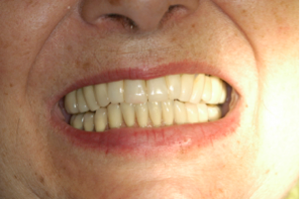

Figuras 7 e 8 – Controle clínico e radiográfico de 10 anos da nova reabilitação implantossuportada realizada pelo Dr. Sérgio Jayme, usando os mesmos implantes justaósseos inferiores realizados pelo Dr. Nilton De Bortoli, 40 anos antes.